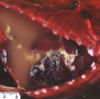

Q

This is a liver. What lesion is shown here?

A

multifocal hepatic abscesses